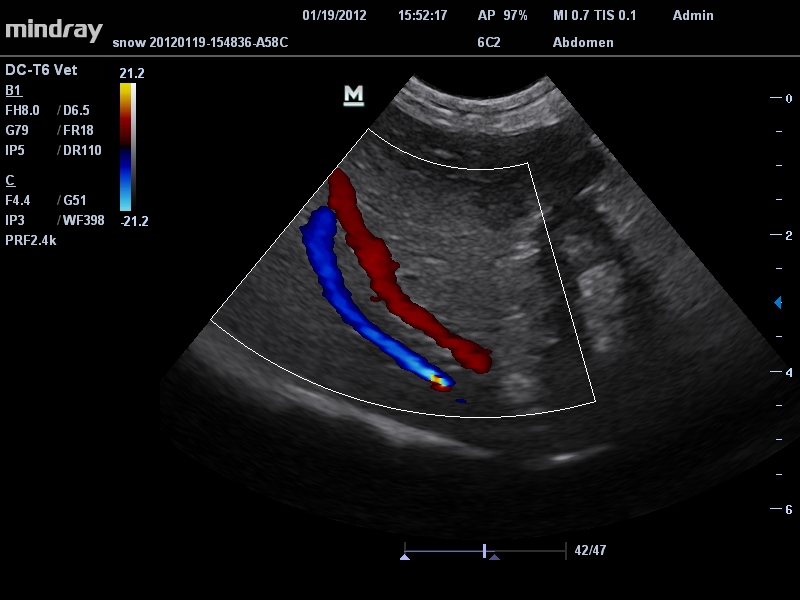

• Микроконвексный датчик Mindray 6C2